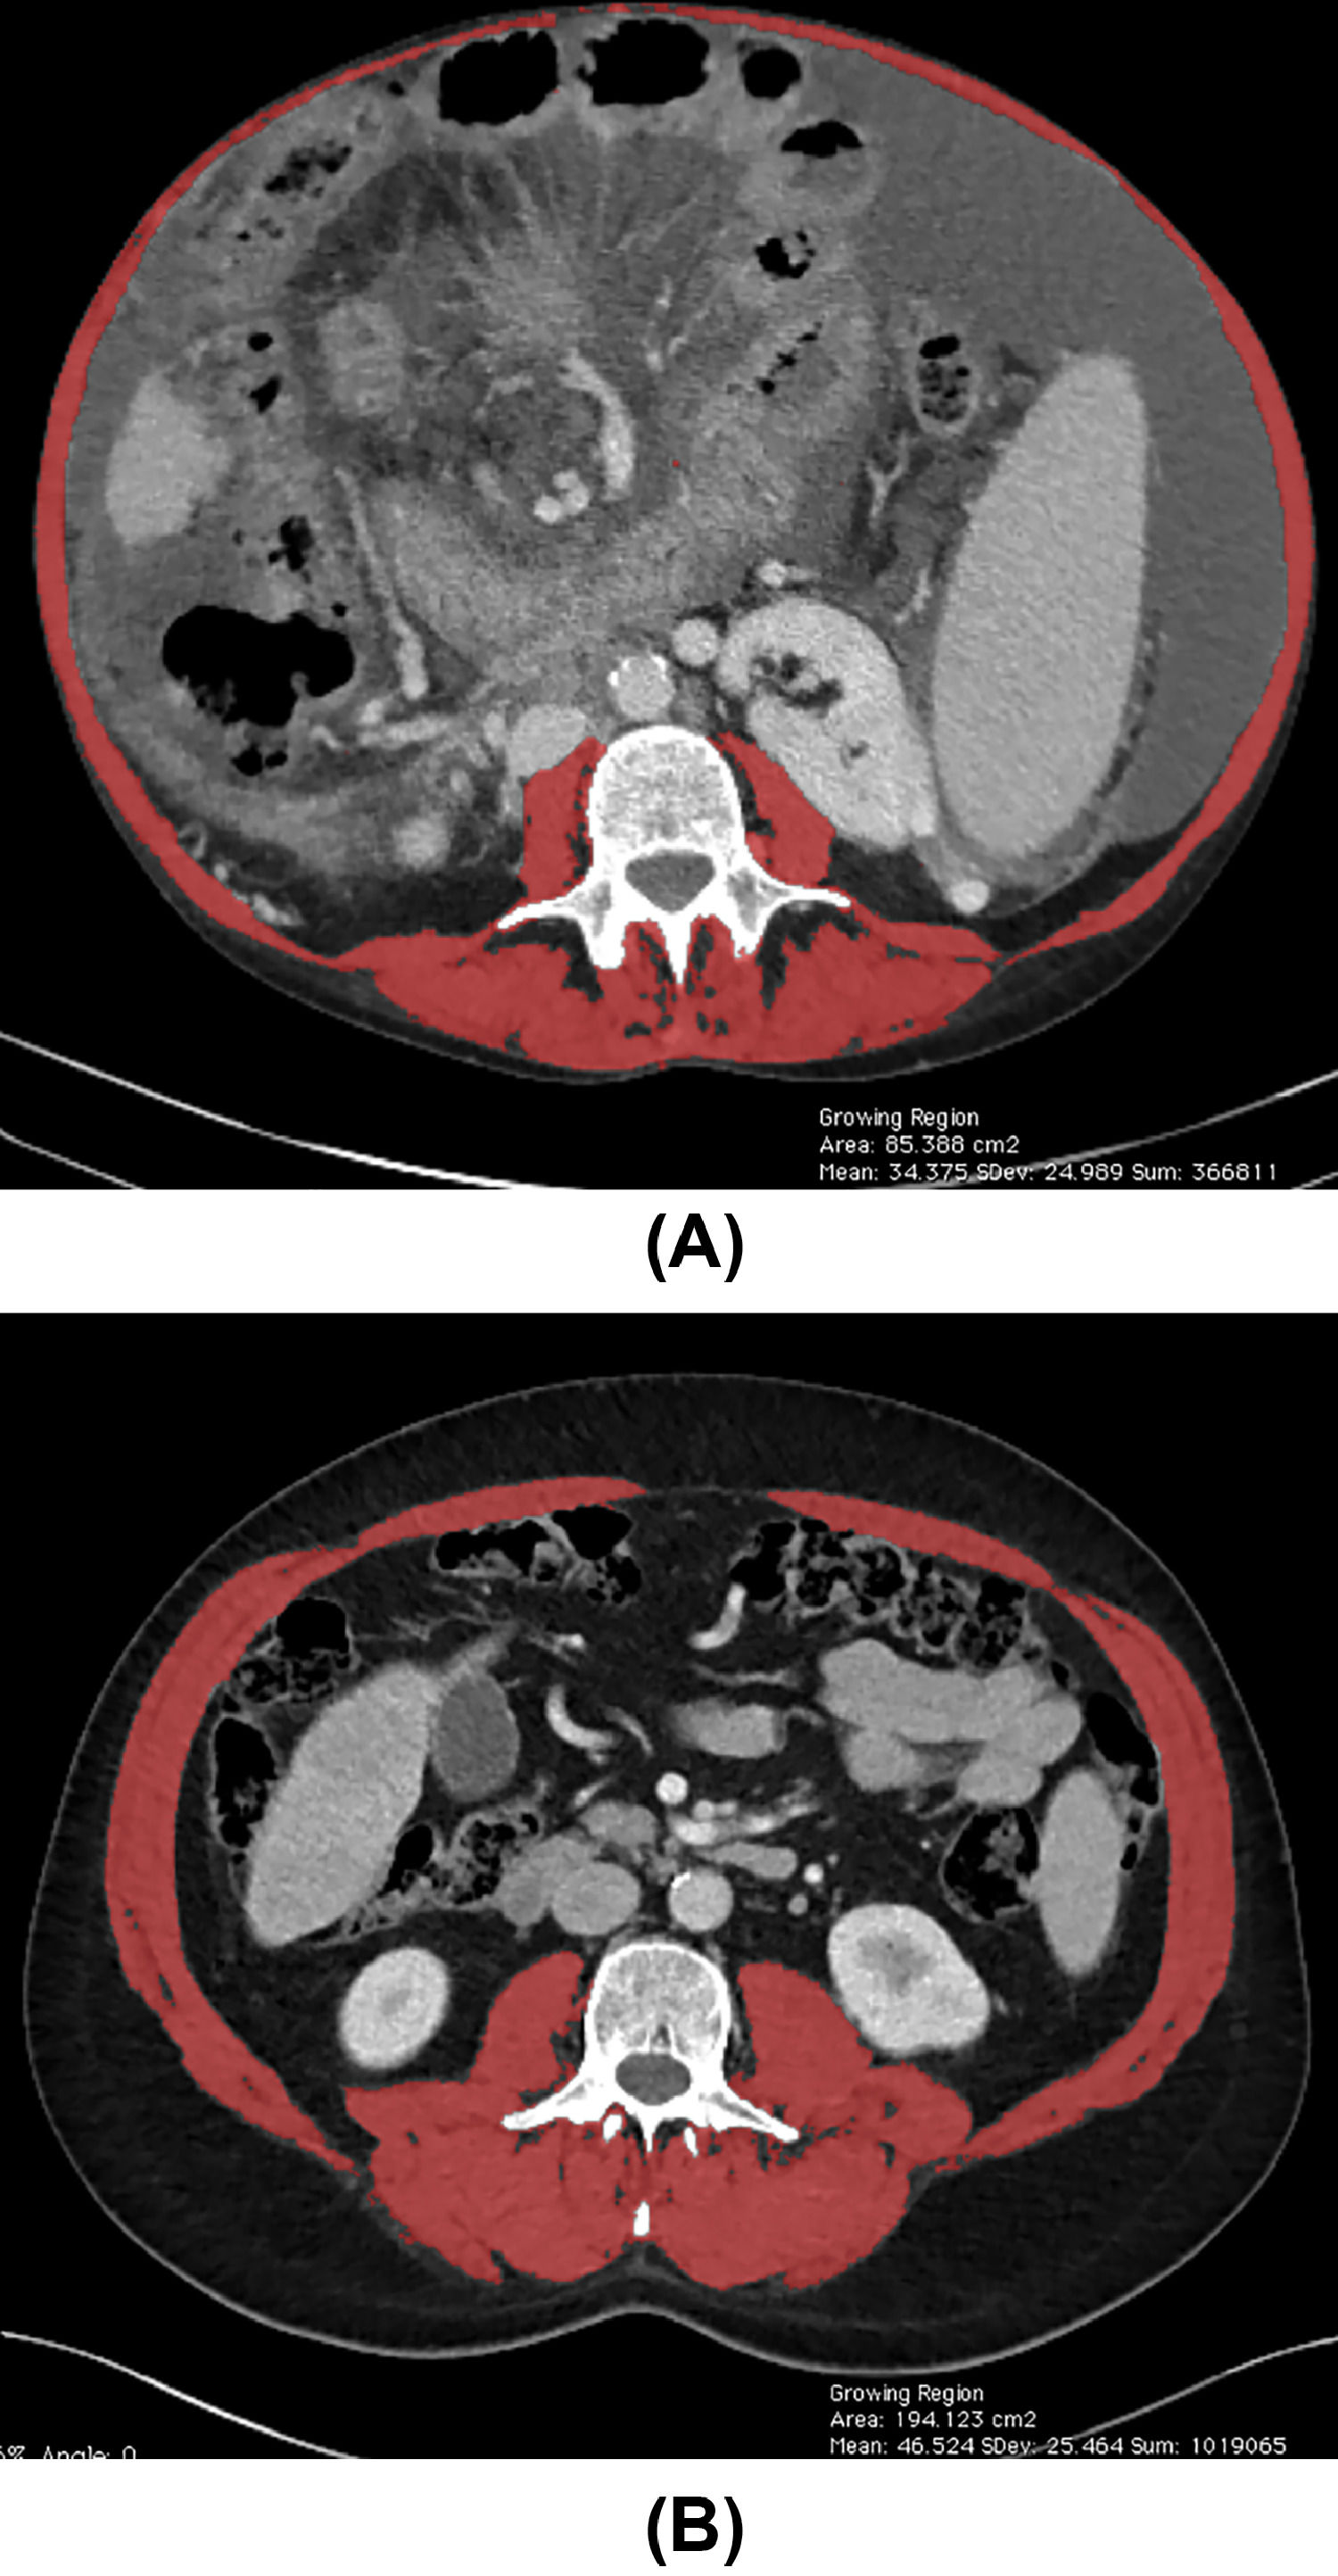

Relationship of Functional Frailty and Radiographic Sarcopenia to Frailty Test Liver Transplant Frailty is an emerging concept in liver transplantation. If they catch themselves, stop the timer,. For each position, start the timer when the patient’s feet are in the correct pose and they have let go of any support. There was consensus that every liver transplant candidate should be assessed at baseline and longitudinally using a standardized frailty tool,. There was. Frailty Test Liver Transplant.